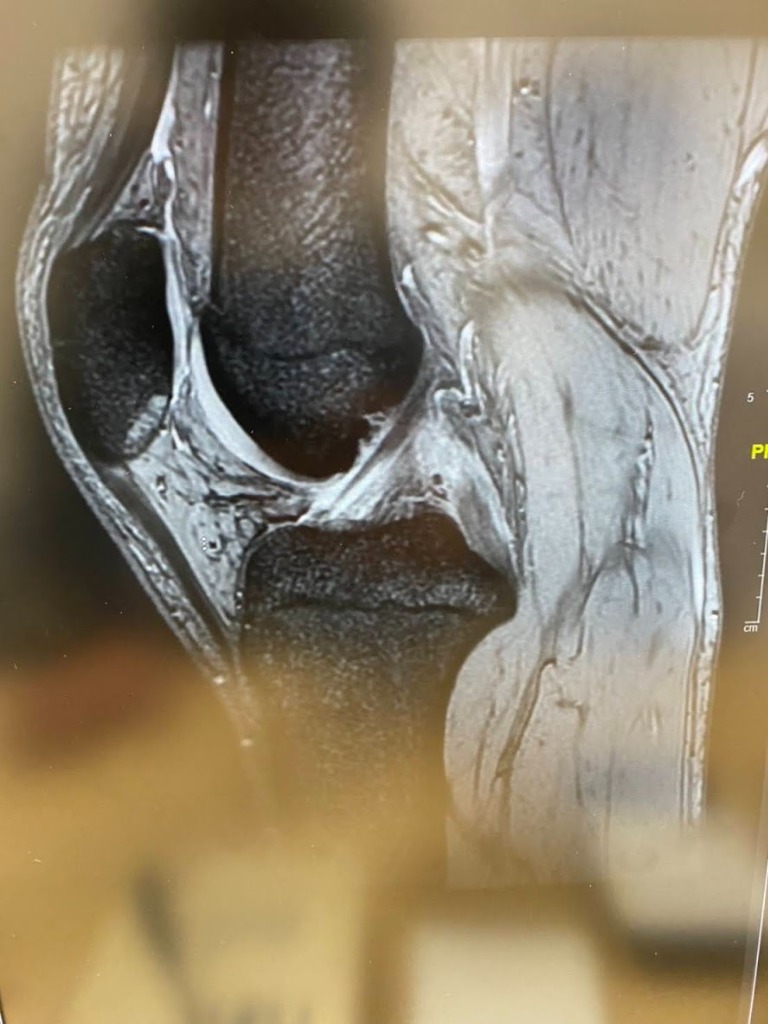

膝関節のPCL(後十字靭帯)損傷